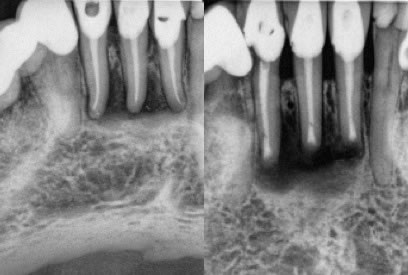

2. Very well done original endodontic therapies.

These would often be scenarios to which we know the specific history of the original root canal treatment, such as treatment that we had originally provided. (figures 4,5) (figures 6,7,8)

Figures 4-5: pre-op / immediate post-op

Original RCT’s performed by myself, but lesions never healed after 2 years and thus apicoectomy performed just a couple months ago. I do not have a long enough recall at this point, but the buccal fistula has fully healed.

Figures 6,7,8: pre-op / post-op / 14 month recall

Original RCT performed by myself and a lesion developed 2 years later. I of course knew this case well and that the tooth was treated in a multi-visit approach using calcium hydroxide. I felt apicoectomy would be a more definitive approach and the healing has been excellent.